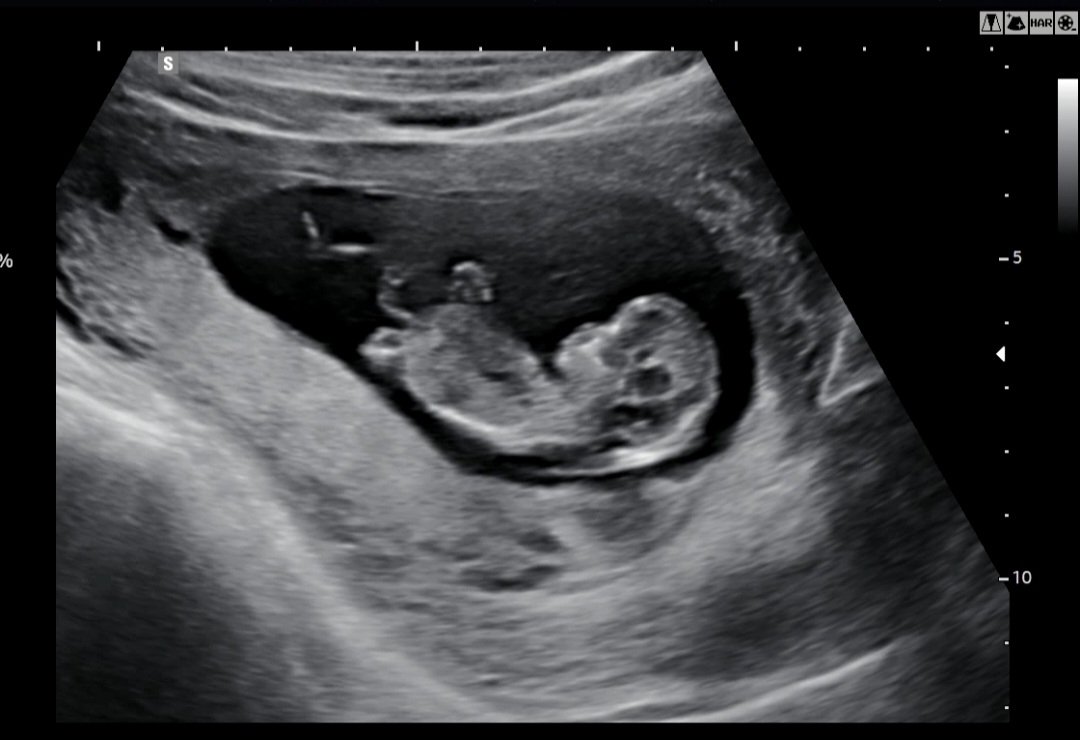

임신 3번만에 드디어 임신12주차...감격... 열무가 잘 누워있어줘서 목투명대도 살짝봐줬는데 정상이라고 하시더라구요ㅜ 정확한 기형아검사는 이번주토요일에하는데 두근두근 머리부터 엉덩이까지 5.29cm 라는데 다리까지하면 더길겠죠..?!ㅜㅜ 내걱정과 다르게 너무 잘자라구 있구나🫶🏻🫶🏻😱